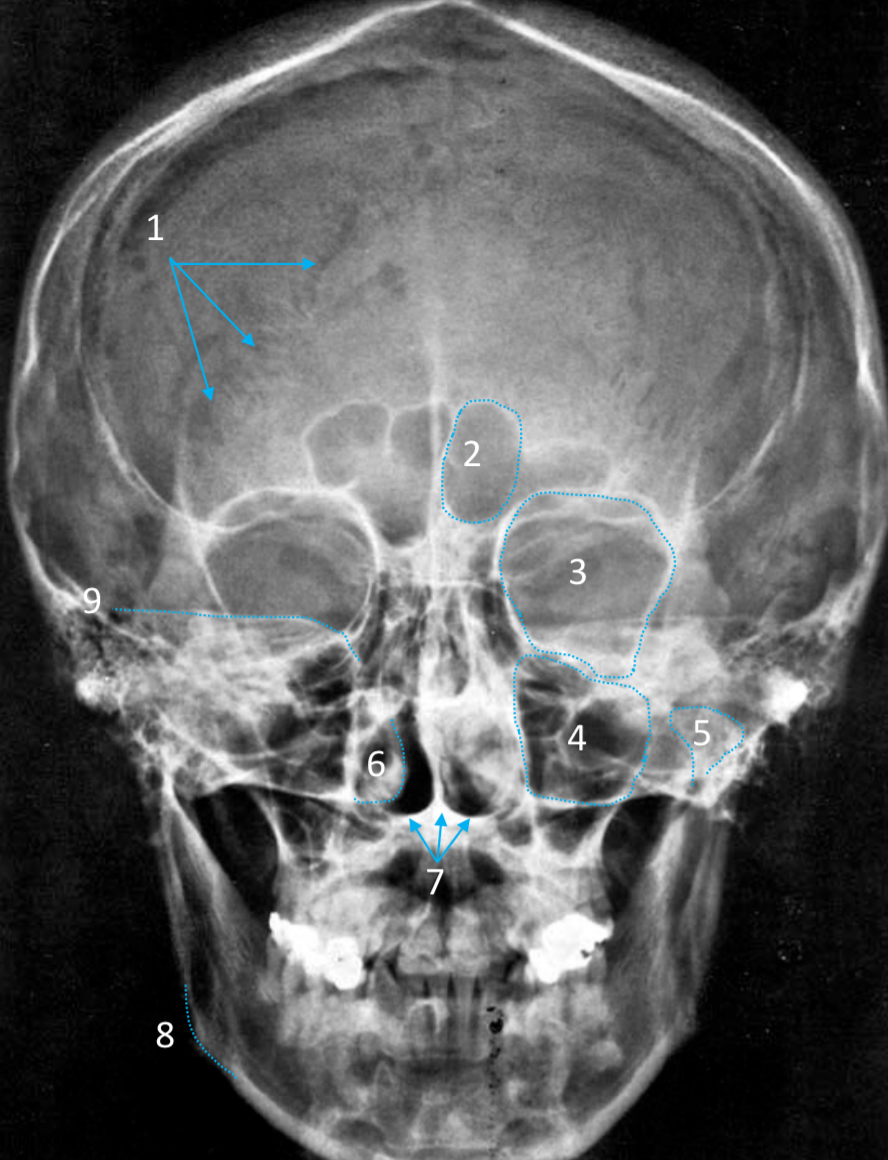

Frontal sinus

ID structure

Pituitary fossa

ID structure

Frontal sinus

ID structure

Orbital margin

Orbit

Maxillary sinus

ID structure

Mandibular condyle

ID structure

Inferior nasal concha

ID structure

Hard palate

ID strucutre

Gonial angle

ID strucutre

Petrous ridge

ID structure

Groove of middle meningeal a.

ID structure

Roof of orbit

ID structure

Frontal sinus

ID structure

Pituitary fossa

ID structure

Petrous ridge

ID structure

Sphenoid sinus

ID structure

Hard palate

ID structure

Mastoid air cells

ID structure

Zygomatic arch

ID structure

Mandibular condyle

ID structure

External auditory meatus

ID structure

Mastoid air cells

ID structure

Foramen magnum

ID structure

Foramen ovale

ID structure

Foramen spinosum

ID structure